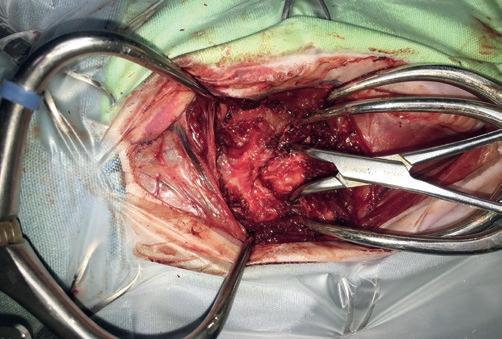

Se presenta el caso de una gata sometida a craneotomía supratemporal para exéresis de un menigioma, en la que se realizó un mantenimiento anestésico intravenoso para mantener una mayor estabilidad hemodinámica durante la cirugía.

Maine Coon, hembra castrada de 8 años, 3,5 kg y condición corporal 5/9, diagnosticada mediante resonancia magnética de una lesión extradural que afectaba a los lóbulos parietal, temporal y occipital (posiblemente meningioma) y que le producía un cuadro de circling, que en el momento de la anestesia estaba controlado gracias al tratamiento con dexametasona 0,15 mg/ kg/24 h. Como otros antecedentes clínicos, la paciente presentaba barro biliar, iniciándose el tratamiento con ácido ursodesoxicólico.